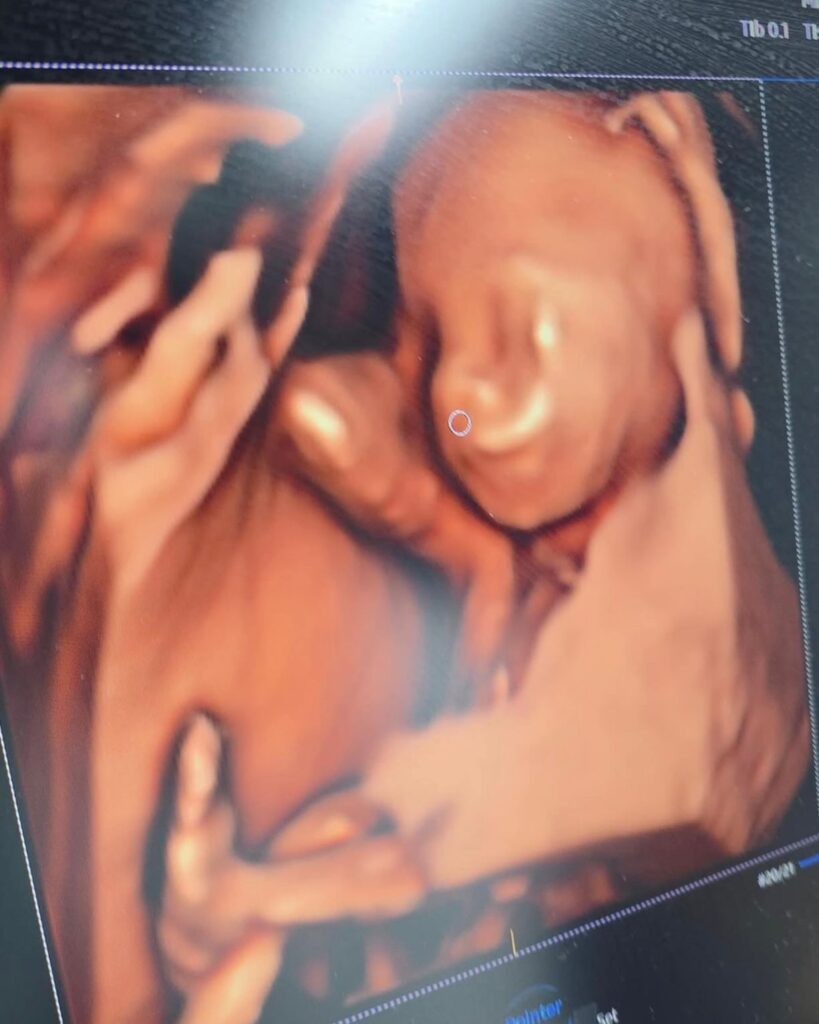

A Prefeitura de Goianésia, pela Secretaria Municipal de Saúde, firmou parceria com a Clínica Móvel Dr. George Morais para oferecer exames gratuitos de ultrassonografia em diversas especialidades. A iniciativa, viabilizada pelo vereador Marcos Pernambuco, ocorre no dia 22 de setembro, no Paço Municipal Laurentino Martins, com distribuição de senhas das 5h30 às 7h.

Os exames incluem ultrassonografia obstétrica, abdome superficial e superior (com jejum de 12 horas), próstata (bexiga cheia), endovaginal, bolsa escrotal, tireoide e mama. Cada paciente pode realizar um exame, ampliando o acesso a diagnósticos essenciais para a comunidade.